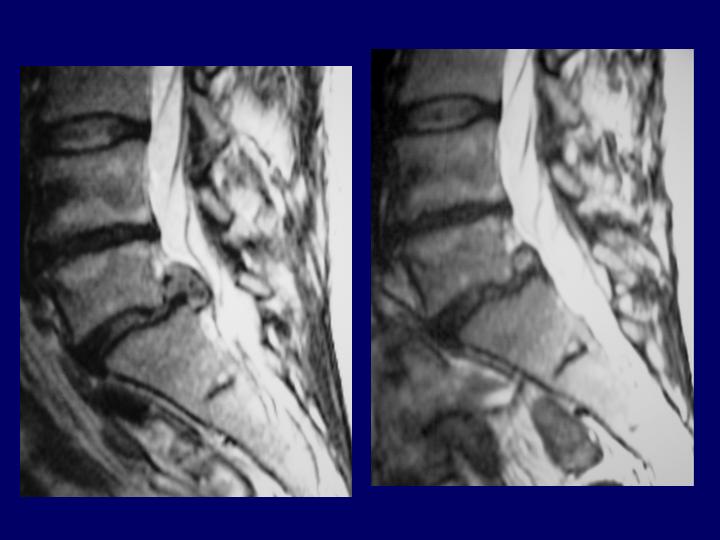

Hernias Discales